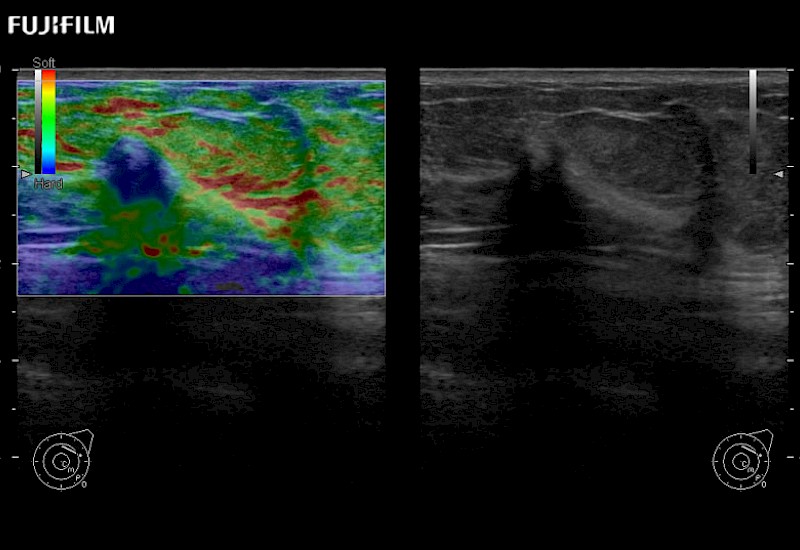

The ARIETTA 750 incorporates all of the proven technologies and functions that medical professionals have come to expect from Fujifilm Healthcare.

ARIETTA 750 is the definitive diagnostic ultrasound solution for any clinical setting - Private Office, Imaging Center, or Hospital. The ARIETTA platform provides the ultimate in clinical performance with its state-of-the-art features and large user-friendly display.

The ARIETTA 650 DI combines trusted Fujifilm Healthcare technologies and features tailored for surgical oncology.

Designed to meet the demands of surgeons, the ARIETTA 650 DI offers precise guidance. Its advanced capabilities and large, intuitive display offer accurate and efficient care in operating rooms and specialized surgical settings.